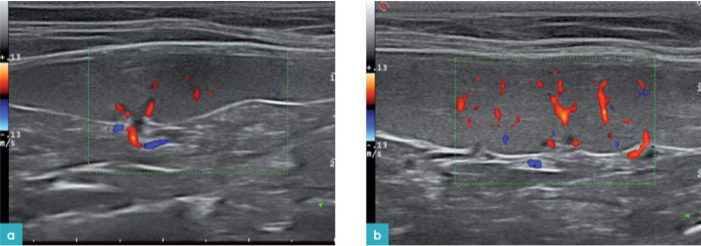

健康动物的脾脏边界清晰,被膜薄而光滑(图2和图3)。脾脏的脏器面的轮廓不规则,是因为在脾门的地方有血管进出。横断面上的脾脏呈三角形(图4)。二维超声图像上很难看到脾动脉进入脾脏,需要使用彩色多普勒才能识别脾动脉(图3)。

最近一项研究提出了判断健康猫脾脏大小和外观评估的新方法(Sayreand Spaulding,2014)。该方法选取脾脏的三个部分进行测量:脾头(近端三分之一)、脾体(中间三分之一部分)和脾尾(远端三分之一部分)。在每个部分测量脾脏的高线(从脏器面到体壁面的垂直距离)。

分别测量脾头和脾尾横截面上的厚度。此时脾脏呈三角形,在脏器面上可见脾脏静脉。把光标放在脏器面上静脉的旁边(但是不要放在血管内),垂直引一条线到达体壁面进行测量,得到脾脏的厚度。要在脾脏的内外侧顶点到达脾门的距离相等的图像上测量脾脏的厚度,避免在斜切面上测量。

在脾脏的长轴(矢状面)上测量牌体的厚度。从脏器面上的血管旁垂直测量到体壁面,得到脾体的厚度(图7)。